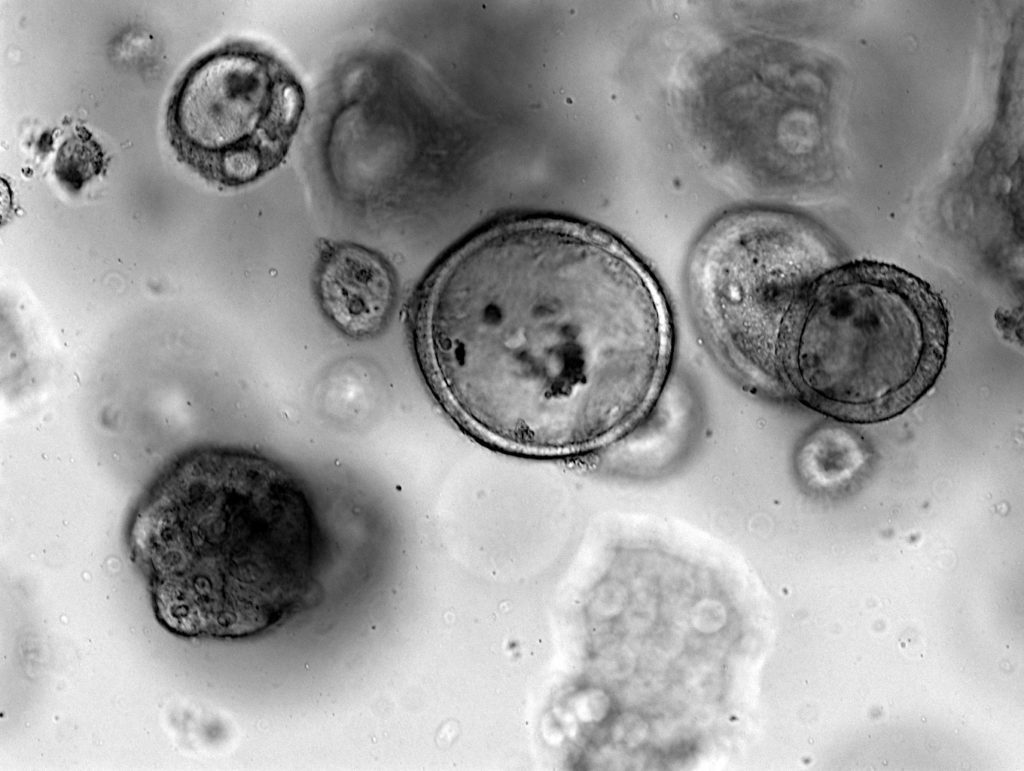

Visualisation of PDX organoid

Triple negative breast cancer derived xenograft organoid

Pancreatic ductal adenocarcinoma derived xenograft organoid

Colorectal cancer derived xenograft organoid